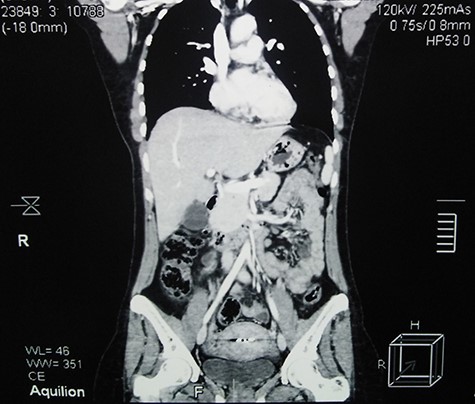

Contrast-enhanced abdominal CT scan shows a large heterogeneous mass adjacent to the inferior margin of the liver measuring (11.5 × 8.5 × 9 cm) and containing calcified areas (red arrows) and necrosis (blue arrow).

Abdominal ultrasound (US) revealed normal findings except for a 9.1 × 7.3 cm heterogeneous mass in the right hypochondrium, and an ~5 cm cystic lesion on the left ovary. Contrast abdominal computed tomography (CT) scan showed a (11.5 × 8.5 × 9 cm) well-defined mass adjacent to the inferior margin of the liver with calcified areas (Fig. 1). Para-aortic lymph nodes were not enlarged.